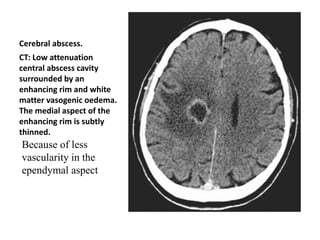

Cerebral abscess.

CT: Low attenuation

central abscess cavity

surrounded by an

enhancing rim and white

matter vasogenic oedema.

The medial aspect of the

enhancing rim is subtly

thinned.

Because of less

vascularity in the

ependymal aspect

Cerebral abscess. CT: Lowattenuation central abscess cavity surrounded by an enhancing rim and white matter vasogenic oedema. The medial aspect of the enhancing rim is subtly thinned. Because of less vascularity in the ependymal aspect